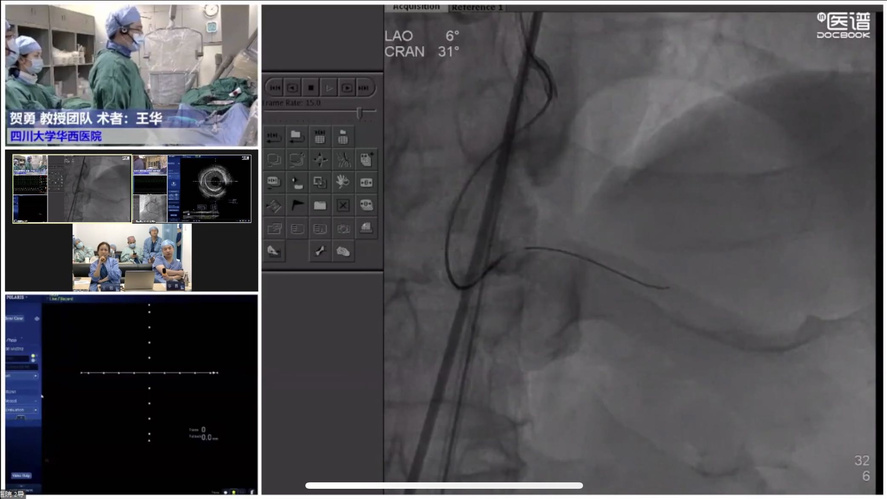

COE卓越中心成立旨在实现头部、地市、县域各医疗中心的联动,实现远程会诊与指导交流。疫情虽然隔绝各地区线下交流,但技术持续发展,远程需求快速增长,必将成为未来发展大趋势。其次希望通过COE中心将多年发展的影像数据进行收集整理发掘更多价值。第三是标准化培训体系建立,既可开展线上远程教学又可在疫情缓解时线下手把手教学,实现上下实时互动。波士顿科学始终对国内影像学与功能学技术的发展充满信心,也希望在波科本土化的进程中,与中国专家共同促进技术创新,服务广大中国患者。会议期间,四川大学华西医院、西安交通大学第一附属医院、南方医科大学南方医院、新疆医科大学第一附属医院、宁夏医科大学总医院心脑血管病医院联袂呈现17例高质量手术直播,所有与会专家各抒己见,畅谈影像技术实战应用。其中四川大学华西医院何森教授带来IVUS指导下LAD重度狭窄伴钙化手术一例。陈勇教授演示一例IVUS指导下的多支血管病变手术;周名纲教授演示一例一月内二次处理的多支病变复杂手术。王勉教授演示一例IVUS指导下逆向开通LAD慢性次全闭塞手术;黄宝涛教授带来了一例IVUS指导下旋磨处理LAD严重钙化病变;李晨教授演示了一例IVSU指导下开通无残端CTO病变的病例。西安交通大学第一附属医院郭宁、张勇教授团队带来造影剂过敏患者PCI治疗,通过IVUS不仅明确病变部位的斑块性质及血管解剖情况,同时确定支架落脚点位置及支架选择。最后在IVUS指导下顺利植入三枚支架,充分展示IVUS对指导低造影剂PCI的临床价值。由南方医科大学南方医院修建成、韩渊、梁鸿彬教授团队带来IVUS指导前降支CTO无残端的病例则先后在对角支、间隔支行IVUS找到前降支开口残端,同时IVUS显示,前降支开口后走行与间隔支夹角较小,近乎平行走行。明确解剖特点后果断决定逆向策略,最终在IVUS指导下,逆向导丝成功进入前降至病变部位远端建立导丝轨道,手术迎来完美结果。宁夏医科大学总医院心脑血管病医院仇玉民、胡光欣教授带来一例右冠CTO病例,残端似乎存在微通道,本计划行ADR,首次尝试正向开通时选择波士顿科学Sentai导丝家族Fighter导丝,仇教授提到该款导丝操控性极佳,头端硬度1.5g,外径0.09"直接通过微通道越过病变部位到达右冠远端,成功建立轨道。正确选择导丝取得开门红后,在IVUS指导下顺利植入一枚支架,迅速完成了这例颇具挑战的手术。精彩的手术演示不仅深度传递腔内影像学与功能学指导下优化PCI治疗的理念,更详细阐述IVUS的规范操作和读图技巧,在理论与实践两方面,实现知行合一。